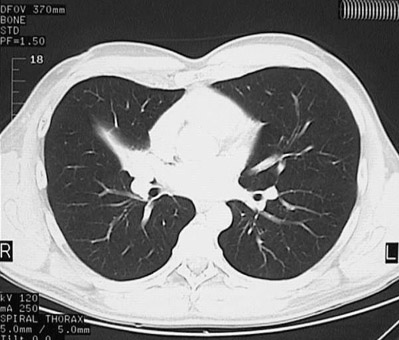

This chest CT scan with "lung window" demonstrates the same bronchial carcinoid tumor that is causing obstruction with atelectasis of the right middle lobe.